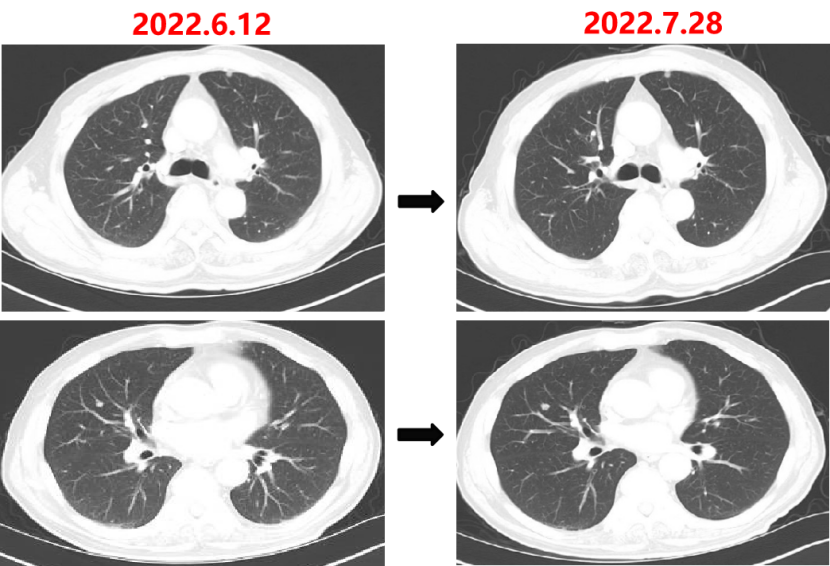

Q1 对于晚期转移性结直肠癌患者,目前,免疫治疗在新辅助治疗中的研究进展和临床应用如何? 结直肠癌是全球第三大肿瘤,转移性结直肠癌的5年生存率只有14%,治疗手段包括手术、化疗、放疗和靶向治疗等。免疫检查点抑制剂的出现也改写诊疗指南。大肠癌dMMR/MSI-H亚型约占所有病例的15%和mCRC病例的5%。由于dMMR/MSI-H的高突变率,肿瘤具有高免疫原性,使其能够激活免疫系统的抗肿瘤作用。 KEYNOTE-177这是一项三期国际开放标签随机对照研究,入选MSI-H/dMMR的IV期结直肠癌患者,比较帕博利珠单抗治疗(200 mg,每3周1次,最多35个周期)与在一线中使用或不使用抗VEGF或抗EGFR单克隆抗体的标准双药化疗,主要终点是PFS和OS。结果显示,帕博利珠单抗组患者的中位PFS时间为16.5个月 VS 8.2个月;3年PFS率分别为42% VS 11%,3年OS率分别为61% VS 50%。帕博利珠单抗组ORR为45.1%(20例完全缓解,49例部分缓解),化疗组为33.1%(6例完全缓解,45例部分缓解);帕博利珠单抗组83.5%的患者至少维持缓解了2年;在化疗组中,只有33.6%的患者缓解持续时间≥2年。KEYNOTE-177研究证实了帕博利珠单抗可以作为MSI-H或dMMR患者的一线标准治疗。 在2021版CSCO结直肠癌诊疗指南中,MSI-H结直肠癌姑息一至三线均推荐免疫治疗,其中帕博利珠单抗作为一线治疗的一级推荐;CheckMate-142研究选择MSI-H/dMMR转移性结直肠癌患者,单免后线vs双免后线vs 双免一线:ORR 39% vs 65% vs 71%,DCR 69% vs 81% vs 84%,一线双免完全缓解率为13%。结果说明双免好于单免,一线好于后线。CheckMate-142研究具有划时代意义,它将免疫治疗从后线前移到一线。 COMMIT研究是一项前瞻随机开放标签的三期临床研究,评估了阿特珠单抗单药治疗对比mFOLFOX6(氟尿嘧啶、奥沙利铂、亚叶酸钙)+贝伐珠单抗+阿特珠单抗一线治疗dMMR或MSI-H转移性结直肠癌的疗效和安全性,目前该试验还在进行中。未来该项研究的结果将回答对于MSI-H晚期结直肠癌,在一线免疫治疗的基础上联合化疗和抗血管靶向药物是否可以进一步提高免疫治疗的疗效。 CheckMate 8HW是另一项随机对照三期临床研究,在一线治疗dMMR或MSI-H转移性结直肠癌中,比较纳武利尤单抗单药、纳武利尤单抗联合伊匹木单抗以及研究者选择的化疗这3种方案的疗效。这项研究将头对头地比较对于MSI-H晚期结直肠癌双免联合是否优于单免的疗效。 Q2 对于MSI-H/dMMR型局部晚期结直肠癌(LACRC),新辅助免疫治疗探索的进展与应用前景如何?有哪些潜在预测疗效的生物标志物? 对于MSI-H/dMMR型局部晚期结直肠癌患者,新辅助免疫治疗可以在肿瘤手术前,提前使患者的免疫系统识别肿瘤细胞,从而使患者的免疫系统更好地产生免疫应答。目前结直肠癌新辅助治疗的探索均为二期研究,探索模式多为双免疫或免疫联合化疗方案,直肠癌多为免疫联合放化疗(同步或序贯)的模式。 NICHE研究是探索纳武利尤单抗联合伊匹木单抗用于Ⅰ-Ⅲ期结肠癌新辅助治疗的二期临床研究,研究共纳入40例结肠癌患者,其中21例为dMMR,20例为pMMR(1例患者同时为pMMR和dMMR),81%的dMMR患者和40%的pMMR患者为临床Ⅲ期结肠癌。患者在接受首次免疫治疗后不迟于6周内接受结肠癌手术,dMMR结肠癌缓解率100%,其中完全缓解的患者占60%,MPR为95%;pMMR治疗组27%的患者也对免疫治疗产生了良好的应答。 NICHE2研究,纳入更多患者,探寻非转移性dMMR结直肠癌患者双免治疗(伊匹木单抗+纳武利尤单抗)的疗效,主要终点为安全性,3年无病生存期。结果显示:MPR率95%,PCR率67%,中位随访13.1个月后没有患者出现疾病复发,毒性可耐受。 NCT04165772研究(前瞻性,单臂,Ⅱ期研究),Ⅱ期和Ⅲ期患者接受新辅助dostarlimab(多塔利单抗)共6个月,结果显示CCR率为100%。 PICC研究是特瑞普利单抗联合或不联合塞莱昔布新辅助治疗错配修复蛋白缺陷或微卫星高度不稳定的局部进展期结直肠癌的双臂随机Ⅱ期临床试验,结果显示完全缓解率高达88%,进一步表明dMMR结直肠癌免疫疗效惊人,潜在替代放化疗及手术。 对于MSI-H或dMMR结直肠癌,NCCN结直肠癌指南中,新辅助治疗增加纳武利尤单抗±伊匹木单抗或帕博利珠单抗单药方案;转化治疗可以选择双免疫或单免疫用药方案。 但并非所有患者都能从免疫治疗中获益,故筛选免疫治疗的疗效预测生物标志物将显得尤为重要。近年来研究主要集中在包括MSI-H、PD-L1过表达、TMB-H(TPS3645)、POLE或POLD1基因突变、PI3K/AKT/mTOR通路、新抗原(身份和数量)、免疫系统状态(免疫细胞特征、T细胞受体相关)等。 Q3 您如何看待对于临床中MSI-H/dMMR 转移性结直肠癌患者使用免疫治疗,部分患者仍然会出现耐药问题? Q4 晚期结直肠癌通常预后相对较差、患者生存期不长,依然是我国困扰结直肠肿瘤治疗的瓶颈问题,但有治愈的可能,此时临床医生制定正确合理用药方案尤为重要。今年上半年发布的CACA-RC指南推荐不适合强烈治疗患者应用曲氟尿苷替匹嘧啶片(TAS-102)联合贝伐珠单抗,作为晚期不可切除结直肠癌姑息一线治疗方案。请您谈谈该推荐治疗对我国晚期不可切除结直肠癌患者的临床治疗带来怎样的获益? 今年上半年CACA-RC指南推荐了不适合强烈治疗的患者应用TAS-102联合贝伐珠单抗作为不可切结直肠癌一线治疗方案,是在不可切除晚期结直肠癌一线治疗中石破天惊的一项突破。晚期mCRC的标准化疗方案在指南中是以奥沙利铂或伊立替康为基础的FOLFOX和FOLFIRI方案,在此基础上,可以根据基因分型联合西妥昔单抗或者贝伐珠单抗,但是依旧有部分患者身体状况无法耐受加强化疗,针对这一类患者的治疗方案选择非常有限,且预后情况并不理想。TAS-102+贝伐珠单抗治疗方案毒副反应相对较低,(临床试验提示比贝伐珠单抗联合卡培他滨效果好)疗效确切,在未来较长一段时间内,尤其是目前疫情肆虐,患者不方便住院治疗时,TAS-102可作为国内不适合强烈治疗的mCRC患者及老年患者的一线治疗优选方案,并为患者带来持续的、更优的生存获益。 二 病例分享 专家简介 王峰 教授 医学博士,副主任医师,硕士研究生导师 滨州医学院附属医院肿瘤科副主任 澳大利亚悉尼维斯迈医学中心访问学者 中华医学会放射肿瘤治疗学分会骨与软组织学组委员 中国临床肿瘤学会(CSCO)神经系统肿瘤专家委员会委员 山东省医师协会肿瘤精准医疗医师分会常务委员 山东省医师协会肿瘤放疗医师分会委员 山东省抗癌协会消化道肿瘤分会常务委员 山东省医学会咽喉肿瘤多学科联合委员会委员 山东省医学会烟草病学与戒烟多学科联合委员会委员 山东省健康管理协会消化道肿瘤防治分会常务委员 山东省医学会放射肿瘤学分会青年委员 山东省医学会妇科肿瘤多学科联合委员会委员 滨州市医学会放射肿瘤学专业委员会副主任委员 01 基本情况 (一)基本信息 患者男性,65岁,于2021-08-26第一次入滨州医学院附属医院风湿免疫科。 主诉:发作性右踝关节肿痛3年,再发1月。 查体:双足第一跖趾关节可见红肿,伴局部皮温升高。 既往史、个人史:既往脑梗死病史7年余,未遗留后遗症;有“膀胱结石”病史1年余,未系统诊治;有“痛风性关节炎”3年余,曾于滨州医学院附属医院风湿免疫科治疗。有高血压病史10年余,最高血压180/110mmHg,口服“吲达帕胺片”,血压控制可。 常规检查发现2次大便潜血阳性。 (二)辅助检查结果 1.肠镜检查 直肠、乙状结肠:直肠距肛门7cm可见一巨大溃疡型病变,表面溃烂,污秽苔,周边环堤样隆起,累及管腔1/3周圈,管腔无狭窄,于病变周边多点活检8块,质脆易出血;乙状结肠见一0.5cm*0.3cm息肉,余黏膜光滑,皱襞清晰,蠕动规律;肛管未见异常。降结肠、横结肠:横结肠见一0.3cm*0.4cm 0-IIa型息肉,表面粗糙,余黏膜光滑,血管纹理清晰,未见异常。 诊断:1.直肠Ca(进展期 溃疡型);2.结肠多发息肉——内镜下冷切除术+息肉摘除术。 2.胸部、上腹部未见明显异常。 直肠MR增强+DWI:直肠距肛缘约5.5cm处肠壁明显不均匀增厚,累及长度约6.0cm,呈等/长T1、等/稍长T2信号,T2压脂呈不均匀高信号,DWI呈高信号,ADC图信号减低,增强扫描呈明显不均匀强化,相应局部管腔狭窄,邻近浆膜面模糊,周缘可见小淋巴结。 02 治疗经过 2021-09-08:于全麻下行全直肠系膜切除+末端回肠预防造瘘术。 术中见:肝脏、胃、腹壁等无转移性结节。肿块位于腹膜返折处,活动度差,侵及浆膜。肠周见明显散在肿大淋巴结。 术后病理:直肠下段中分化腺癌,侵犯外膜下脂肪组织,肿瘤出芽分级(高级别,Bd3),侵犯神经侵犯,未见确切脉管内癌栓;两侧手术切缘、环周切缘及标记切缘内均未查见癌累及,肠周淋巴结内未查见转移癌(0/17)。pTNM分期:pT3N0Mx。免疫组化结果:CK(+),MSH2(+),MSH6(+),MLH1(+),PMS2(+),MDR-1(3+),HER2(3+),P53(3+),Ki-67阳性率约70%。 术后诊断: 1.直肠癌II(pT3NOMO)期术后; 2.结肠多发息肉术后; 3.痛风性关节炎; 4.高血压病(3级 很高危); 5.脑梗死。 CSCO指南: 2021-10-04至2022-06-03:FOLFOX方案化疗10周期(奥沙利铂150mg d1+氟尿嘧啶 0.7g d1+4.4g civ);术后预防性放射治疗DT5000cGy/25f,同步卡培他滨。 2021-11-25至2021-12-06:尿培养提示肺炎克雷伯菌感染,结合泌尿外科、感染科会诊意见,给予左氧氟沙星抗感染治疗。 2022-06-12 肺无法穿刺活检。 基因检测示:(直肠)KRAS/BRAF/NRAS/PIK3CA 基因均未检出突变。伊立替康UGT1A1基因检测结果:非风险基因型。 CSCO指南: 2022-06-20:西妥昔单抗联合FOLFIRI方案治疗(西妥昔单抗900mg d1,伊立替康320mg d1,氟尿嘧啶0.7g iv 4.3g civ)。 2022-07-06:骨髓抑制、腹泻,西妥昔单抗联合FOLFIRI方案治疗(西妥昔单抗900mg d1,伊立替康280mg d1,氟尿嘧啶0.7g iv 4.3g civ)。 疗效对比: 循证依据: C-TASK FORCE研究:首个证实TAS-102联合贝伐珠单抗治疗mCRC的疗效及安全性研究。TAS-102联合贝伐珠单抗是难治性mCRC患者潜在治疗选择,更多临床获益有待进一步研究。 TAS-102联合贝伐珠单抗治疗mPFS时间和mOS时间分别为5.6个月和11.2个月。 TAS-102联合贝伐珠单抗不良反应主要为血液学毒性。 日本大样本RWS:TAS-102和瑞戈非尼不同排序的回顾性研究。 日本大样本RWS:TAS-102单药较瑞戈非尼单药,可显著延长mOS,降低AE。 日本大样本RWS:两药序贯疗效优于单药,且≥65岁先用TAS-102获益更显著。 日本大样本RWS:TAS-102序贯瑞戈非尼组持续治疗时间更长。 2022-07-27至今 给予贝伐珠单抗联合TAS-102治疗期间复查CT评估SD,胃肠道反应不重,骨髓抑制Ⅰ度,耐受性尚可。 *本文仅代表专家观点,并经专家审校。